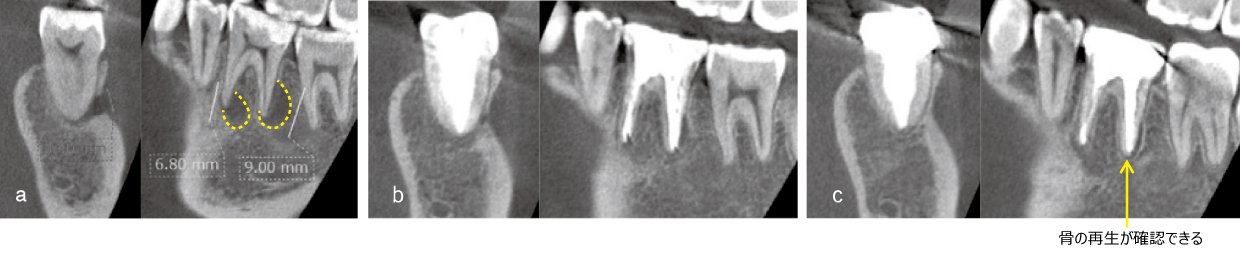

EMAT is a regenerative treatment that revives the "alveolar bone" that supports teeth by activating bone-forming cells called "osteoblasts," which are naturally present in the patient. At the same time, it has the effect of sterilizing bacteria that inhibit the preservation of teeth, so it can be expected to improve the symptoms you are suffering from.